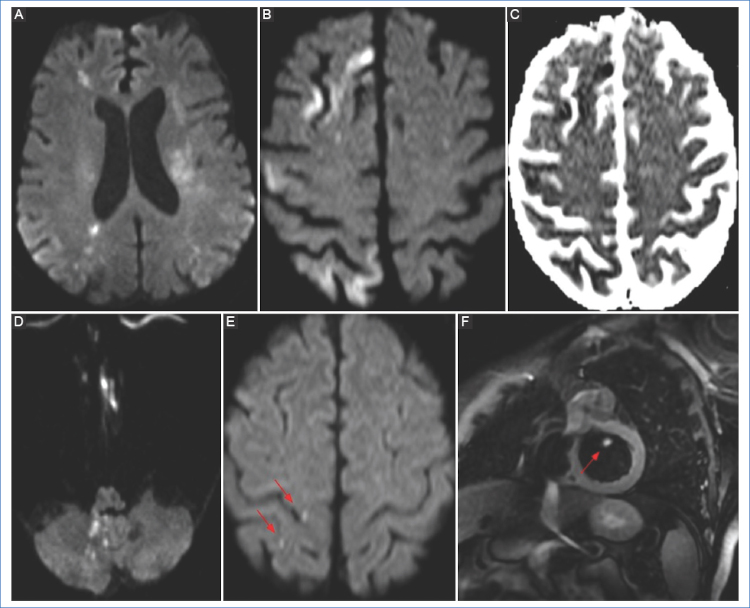

En el caso de las disecciones que involucran el circuito anterior (carotídeo), los patrones más frecuentemente observados son los de embolia cortical (80%) y subcortical, siendo la ACM la más frecuentemente afectada13, así como también infartos en territorio frontera por hipoperfusión y fallo hemodinámico.

Los infartos en territorio frontera se dan en la unión de dos territorios vasculares arteriales y se clasifican en corticales e internos. Se producen por mecanismos hemodinámicos (estenosis u oclusión arterial, hipotensión sistémica y eventos embólicos). Se cree que los infartos corticales en territorio frontera se dan por microembolización de aterosclerosis carotídea o placas vulnerables, o por embolización arterio-arterial precipitada por un episodio de hipotensión sistémica4.

Recientes estudios con resonadores de 3T han descrito un mismatch entre las secuencias SWI/DWI, comparable al mismatch DWI/PWI. En ocasiones podemos observar el core del infarto en la secuencia DWI, y múltiples vasos hipointensos adyacentes en la secuencia de susceptibilidad (mismatch total DWI-SWI), que indicaría tejido cerebral hipoperfundido (penumbra). Esto corresponde a múltiples venas dilatadas y prominentes con una alta concentración de desoxihemoglobina en un tejido que tiene una elevada fracción de extracción de O2.

Fisiopatológicamente este hallazgo corresponde a una relación desoxihemoglobina/oxihemoglobina incrementada, debido a la creciente demanda de oxígeno del tejido cerebral hipoperfundido, aunque no irreversiblemente dañado, siendo un indicador de buena circulación colateral y mejor pronóstico o respuesta al tratamiento19 (Fig. 8). La localización de las hemorragias además nos permitiría dilucidar la etiología, dado que las hemorragias hipertensivas suelen localizarse en los ganglios de la base, tálamo, protuberancia y cerebelo, mientras que las hemorragias lobares son frecuentes en la angiopatía amiloide o en el sangrado de malformaciones vasculares (angiomas cavernosos, malformaciones arteriovenosas, fístulas durales, etc.)3.

Las secuencias angiográficas en la disección de la ACI pueden mostrar oclusión total con preservación del bulbo, o un segmento largo e irregular de estenosis filiforme por estrechez de la luz y engrosamiento parietal debido a hemorragia intramural (signo del collar de perlas) y/o pseudoaneurismas22 (Fig. 9). En la RM de las disecciones extracraneales, las secuencias ponderadas en T1 con saturación grasa son el mejor método para visualización del hematoma mural hiperintenso en las fases subagudas, debido a la metahemoglobina en el lumen falso13.